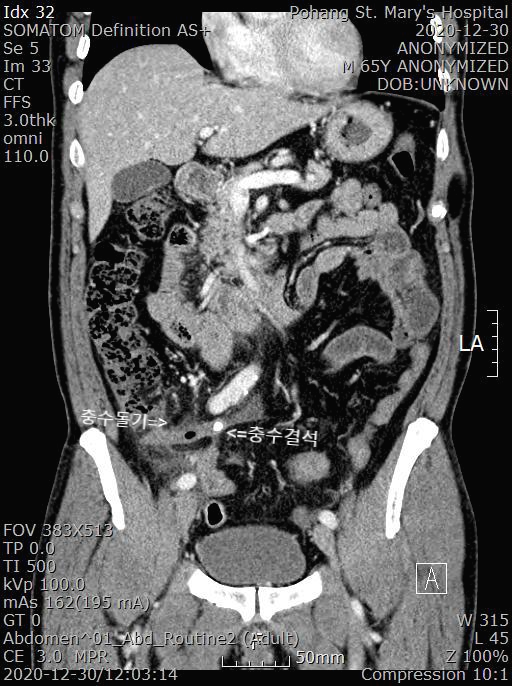

응급실에서 복부 CT를 시행했습니다.

[복부CT 판독]

A 1.1cm, dilated appendix with enhancing wall thickening, periappendiceal fat infiltration and two appendicoliths.

: Perforated appendicitis.

충수돌기가 보이고 염증이 심한 상태이며 충수돌기안에 충수결석(Appendicolith)이 보입니다. 결석이 충수돌기를 막으면서 염증이 발생할 수 있습니다.

또 충수돌기 주위에도 지저분하게 보이는 염증 소견이 보입니다.